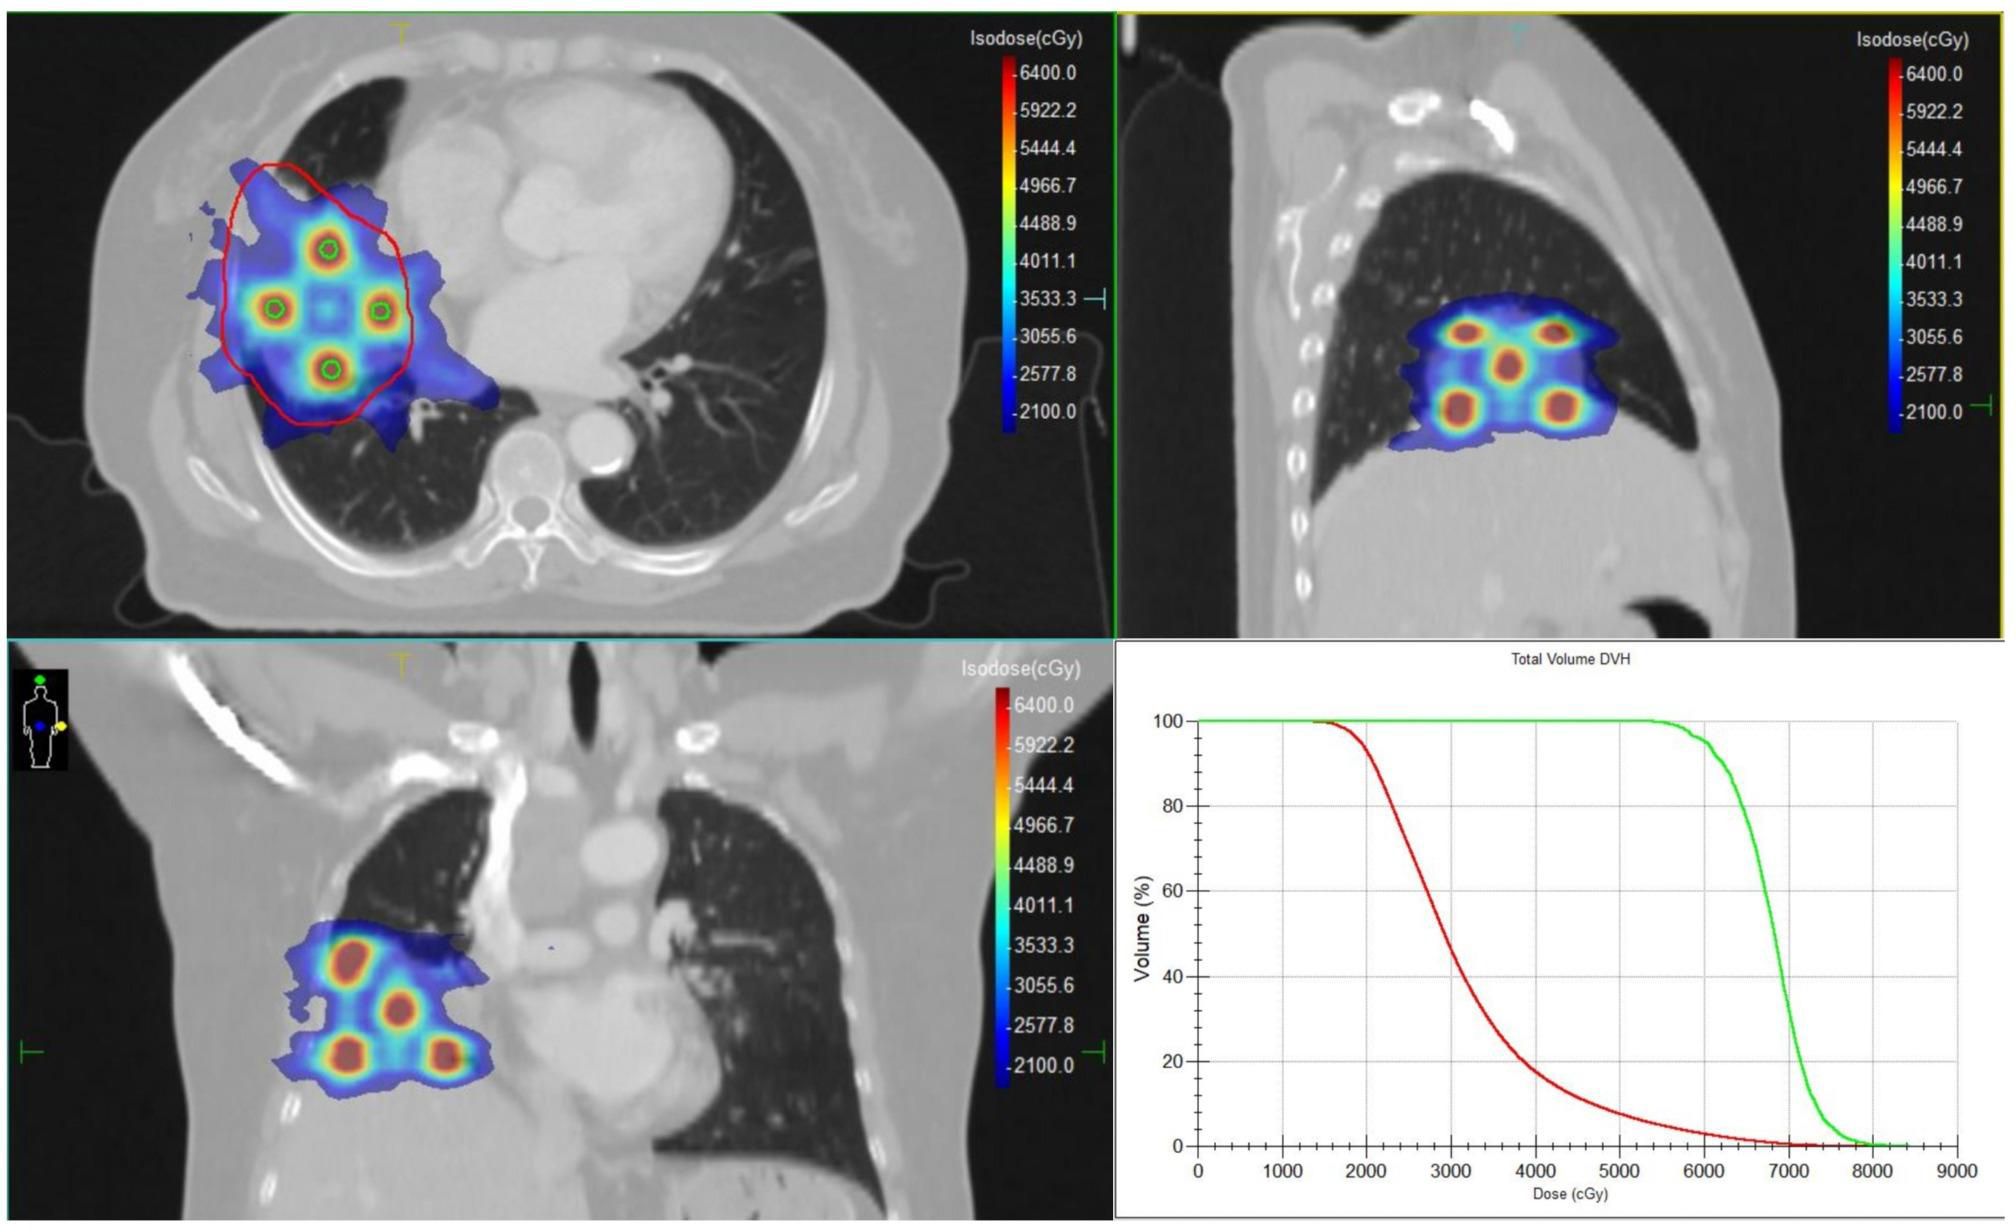

Urachal carcinoma is a rare and aggressive malignancy with limited treatment options, particularly in the metastatic setting. Standardized therapeutic protocols are lacking. This case report describes a 62-year-old female patient who developed pulmonary and mediastinal lymph node metastases more than four years after surgical resection of urachal carcinoma. For this case, a combined regimen of Spatially Fractionated Radiotherapy (SFRT), CapeOX (capecitabine plus oxaliplatin) chemotherapy, and bevacizumab targeted therapy was developed. The treatment course was complicated by grade 4 hematologic toxicity and radiation-induced esophagitis, both of which were successfully managed. To our knowledge, this represents the first documented application of SFRT in urachal carcinoma. Although significant tumor shrinkage was not observed, the patient achieved symptomatic relief, metabolic remission, and stable disease during follow-up.